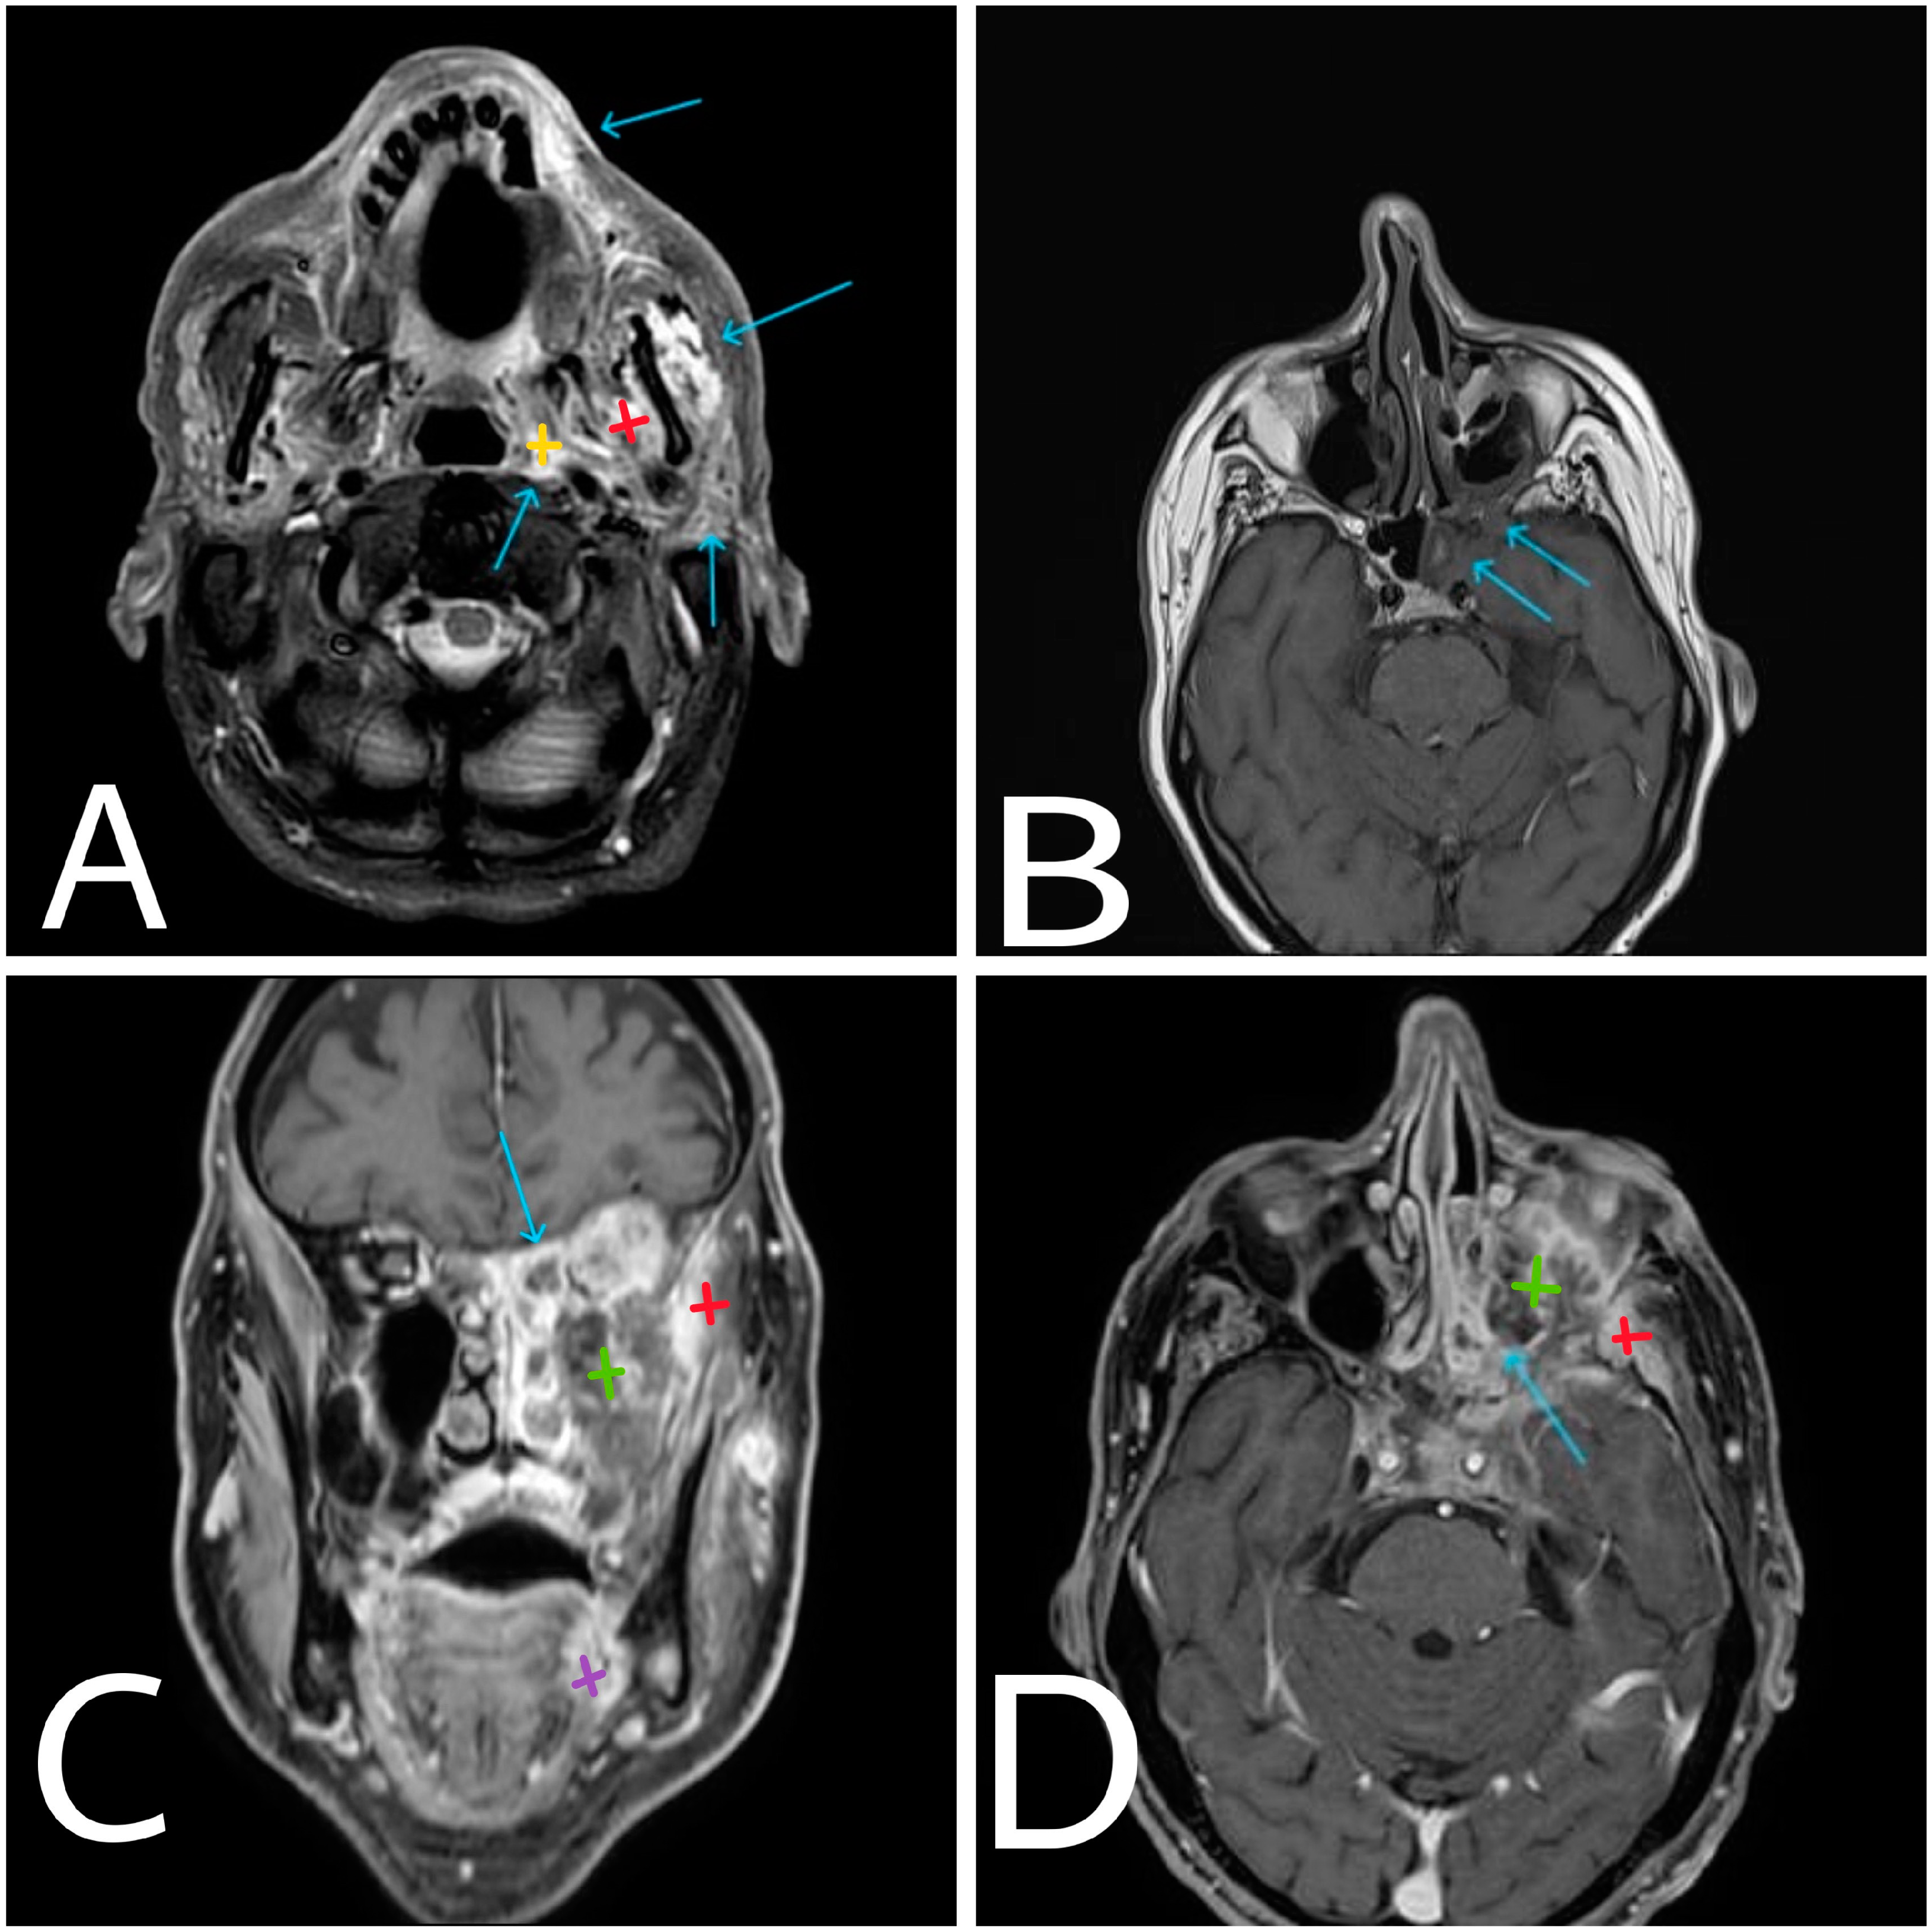

Figure 2. Axial post-contrast enhanced T1-weighted fat-saturated (fs) MRI (A) at the basis of the maxillary sinuses where extensive surrounding tissue involvement is present (arrows). Axial contrast-enhanced T1-weighted (B) and coronal and axial contrast-enhanced T1-weighted fat-saturated (C,D) MRI images of the affected area on the left. Arrows are pointing at the area of intracranial involvement of mid-cerebral fossa. Yellow—left parapharyngeal space. Green—left maxillary sinus. Red—left masticator space. Purple—highly suspicious area for primary neoplasm at the level of left lingual surface.

The CT and MRI (Figure 1) revealed a volume-occupying process, from the posterior wall of the left maxillary sinus with perineural infiltration and involvement of the homolateral trigeminal nerve, intracranial spread in medial cranial fossa and involvement of the cavernous, sphenoidal sinuses and the orbital apex on the left side. The imaging raises a serious suspicion of a more distant origin of the malignant process (Figure 2A—tongue, indicated with a blue arrow), which after a tooth extraction can easily spread to the maxillary sinus.

After the CT was performed, it revealed a volume-occupying lesion in the left maxillary sinus with perineural spread and invasion in the orbit, other sinuses and medial cranial fossa. Sinusitis does not have invasive characteristics, so it was excluded as a diagnostic option. In such cases an endonasal biopsy is the key point to the diagnosis. In our case, the histological result was classified as squamous cell carcinoma G1 (Figure 2).